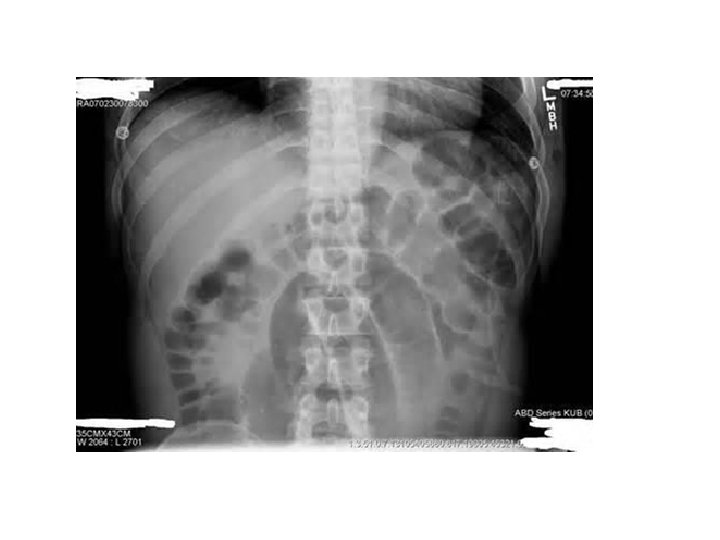

A 45 year old lady presents to the ED with a two day history of abdominal pain. Abdominal examination confirms generalised tenderness. • What is the diagnosis? (1 mark) • Name two other symptoms which the patient may complain of? (1 mark) • What would be your first two steps in your early management of this patient? (1 mark)